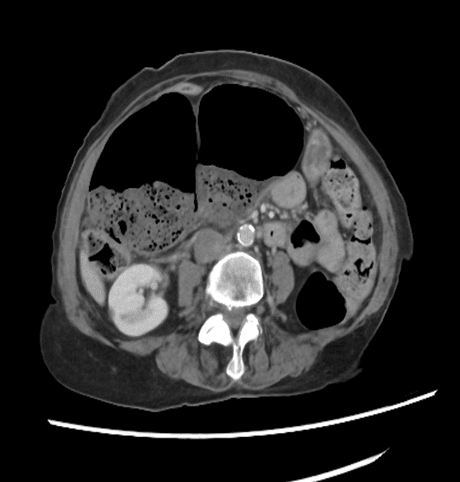

Urology | Oct 17, 2024

Varicocelectomy: An Efficient and Inexpensive Treatment for Male Factor Infertility

Background: A case of varicocele, with primary infertility and a deranged semen parameter, presenting at the surgery outpatient clinic. He...Read More